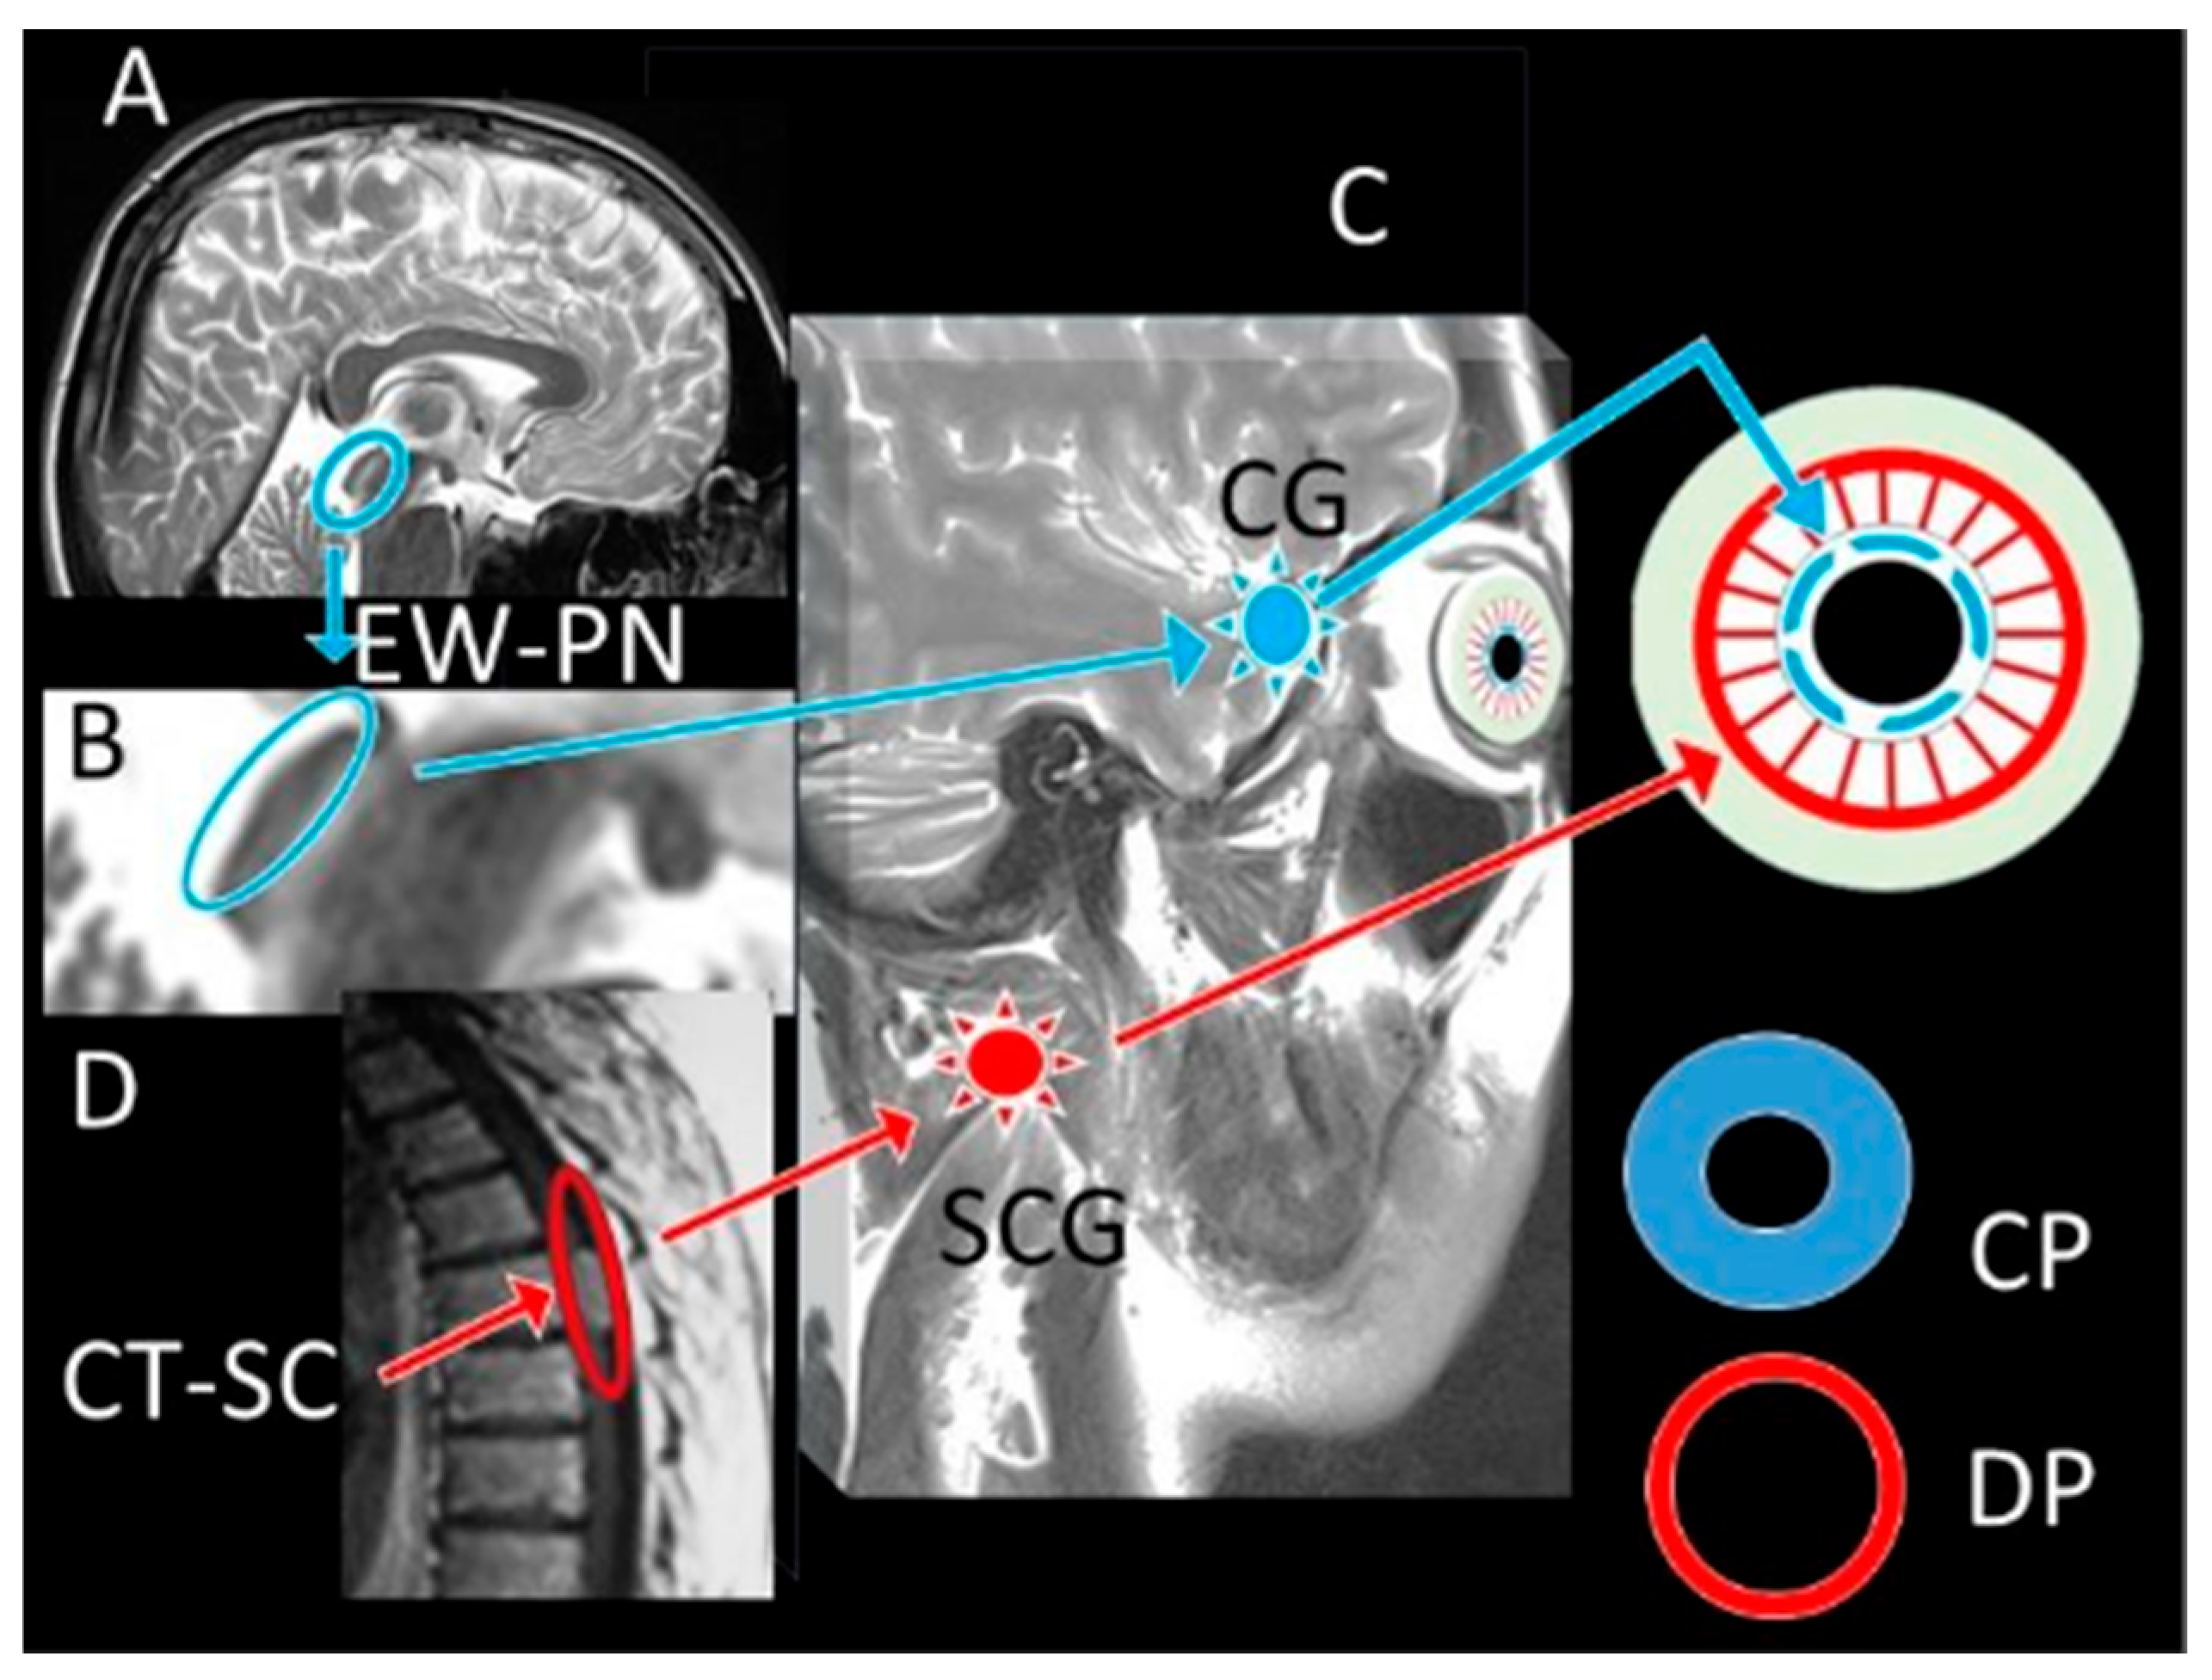

- Wu, F.; Zhao, Y.; Zhang, H. Ocular Autonomic Nervous System: An Update from Anatomy to Physiological Functions. Vision 2022, 6, 6. [Google Scholar] [CrossRef] [PubMed]

- McDougal, D.H.; Gamlin, P.D. Autonomic Control of the Eye. Compr. Physiol. 2015, 5, 439–473. [Google Scholar] [CrossRef]

- Szabadi, E. Functional Organization of the Sympathetic Pathways Controlling the Pupil: Light-Inhibited and Light-Stimulated Pathways. Front. Neurol. 2018, 9, 1069. [Google Scholar] [CrossRef]